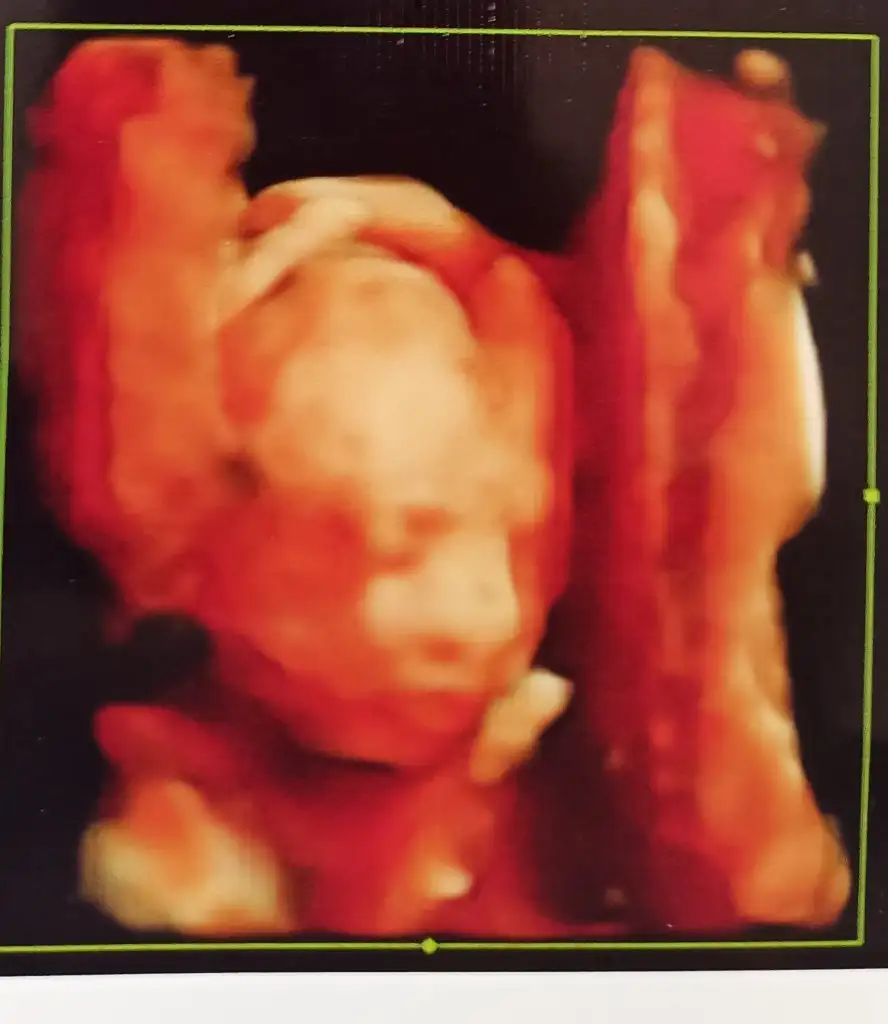

Kizlar bu daha anlattığım muamelenin hafif yanıydi daha kapıdan girdim bu of puff modumda kadın sanki zorla yapıyor bedavaya neyse ya ben iyimser olmaya çalışıyorum ama parlaklık ilerleyen haftalarda geçebilir demi diyorum iyi yaklaşmaya çalışıyorum bana direk diyor ki geçebilir ama geçse de sevinme bi kere parlaklık görüldü mu yeterli mutlaka bi anomali ye işaret edebilir diyor yabi bir kere parlaklık görüldü mu geçse de iyileşti demek değildir dedi Allah im ben de dedim ki yine iyimser bir tavır ile ama hocam bi sey çıkmayada bilir değil mi diyorum tabi o da olabilir diyor

ya karşındaki hamile bir kadın bir can taşıyor yahu . Aslında kizlar Allah var nipt yaptırınca içim daha rahat inşallah sağlıklı olacağına inanıyorum Allah in izniyle yani öyle çok stres yapmadım ama insanın canı sıkılıyor şu tavra .. Ben özele gidiyorum ayda bir zaten orada doktor parlaklık konusunda üstünde pek durmadı bunu takip eden başka şeyler olmalı kalpte beyinde parlaklık gibi tek başına pek anlamı olmaz dedi mesela . Rabbim hepimize sağlıklı evlatlar nasip etsin ve vicdan sahibi doktorlar denk getirsin cidden çok tuaf biriydi